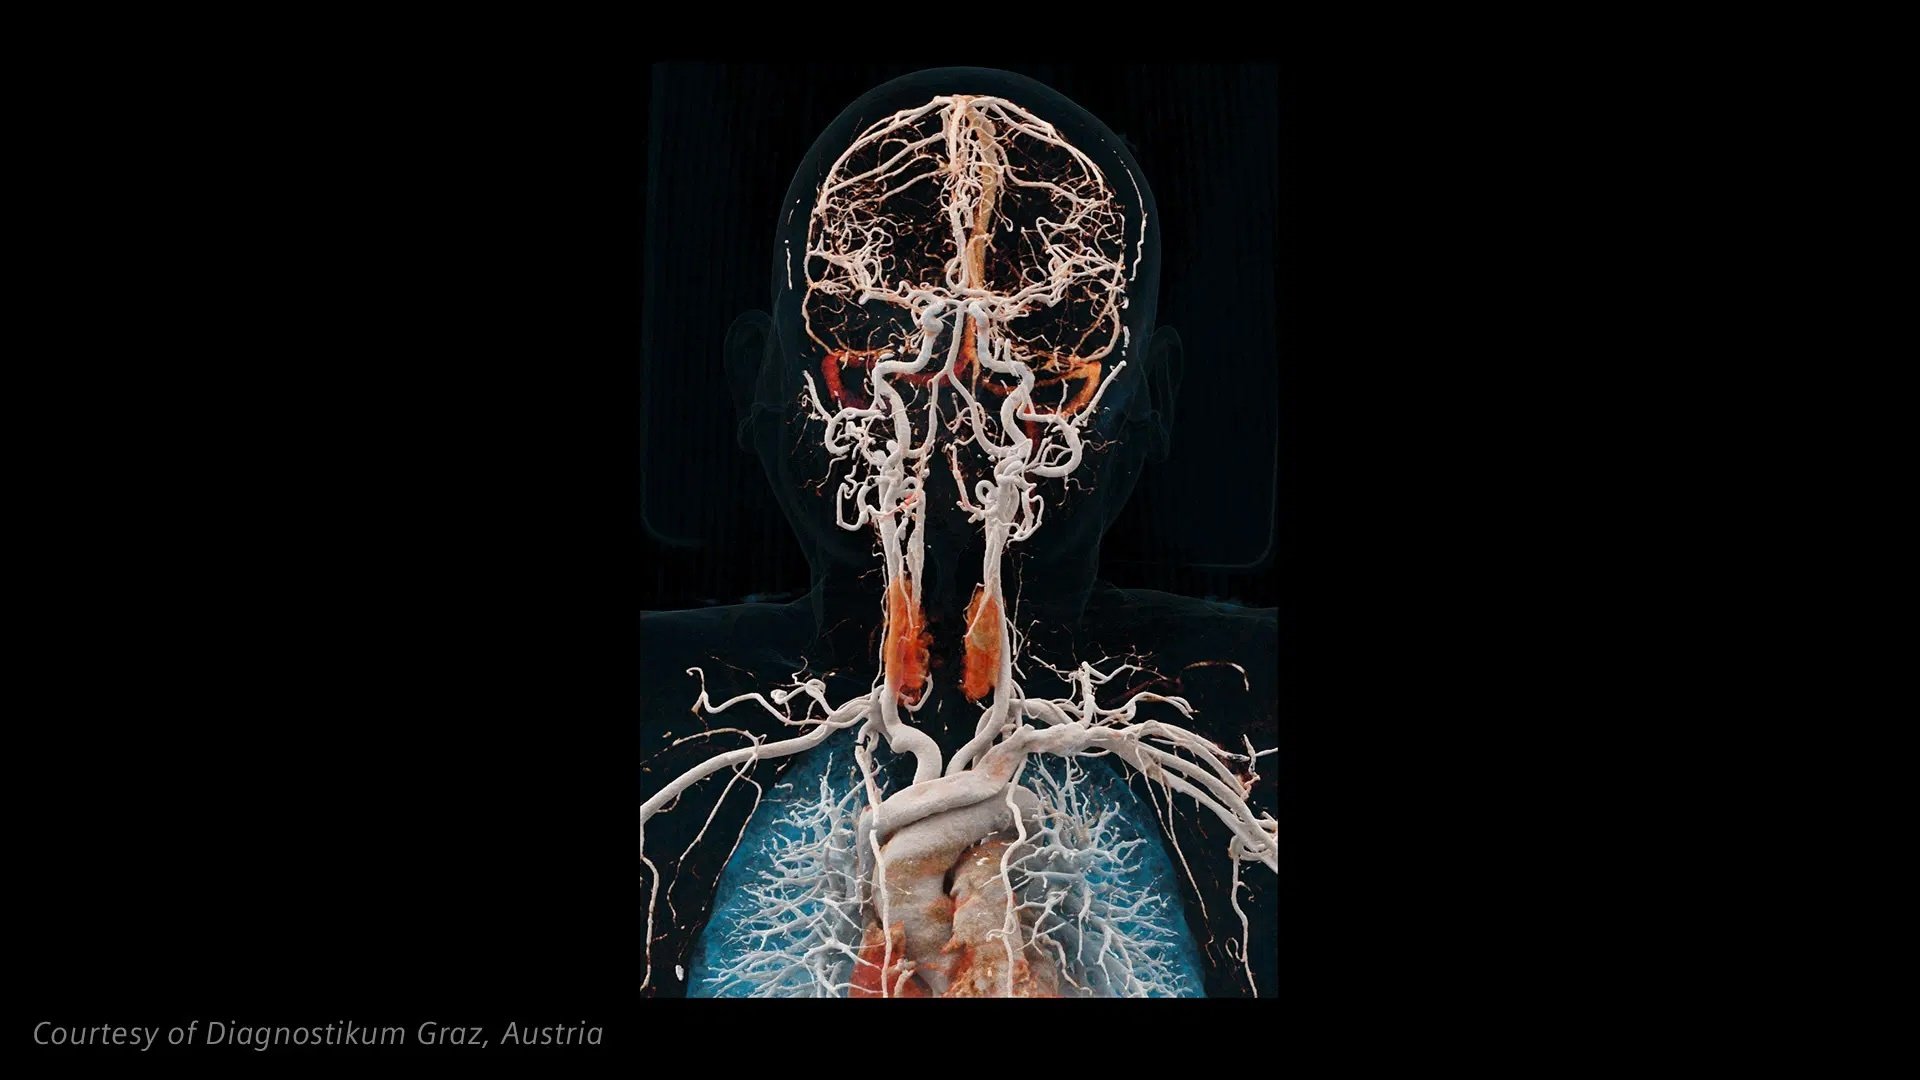

More details in neurology

The unique 0.2 mm slice thickness of NAEOTOM Alpha.Prime with Quantum HD provides high accuracy in neurology and can help change patient diagnoses, from the assessment of stroke, aneurysm, CSF venous fistula or the inner ear.